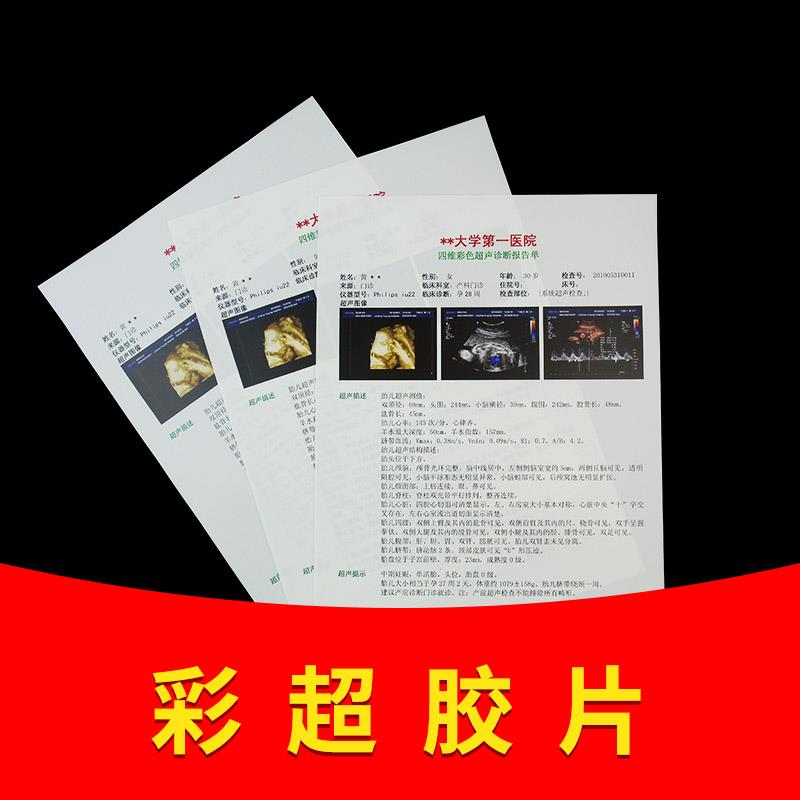

医院用胶片瓷白喷墨片胶片A4胶片胃镜B超四维彩超打印纸100张

淘宝好物 胶片工厂直销店

购买 -

医用超声瓷白喷墨胶片A4激光胶片胃镜B超四维彩超胶片打印纸100张

淘宝好物 胶片工厂

购买 -

医院用胶片彩超打印胶片B超瓷白喷墨A4激光半透三维四维胶片A3

销量38 胶片工厂医院用彩超胶片放射科胶片直卖

购买 -

医用胶片彩超打印胶片纸瓷白喷墨A4激光半透16K彩干式胶片双面A3

销量58 胶片工厂医院用彩超胶片放射科胶片直卖

购买 -

医院用彩超胶片打印纸B超胃镜喷墨瓷白半透明激光干式胶片纸

天猫好物 佰培柏言专卖店

购买 -

医院用胶片瓷白喷墨片胶片A4胶片胃镜B超四维彩超打印纸100张

天猫好物 佰培柏言专卖店

购买 -

81.85医用超声瓷白喷墨胶片A4激光胶片胃镜B超四维彩超胶片打印纸100张

淘宝好物 春贵利民商城

2.45元优惠券